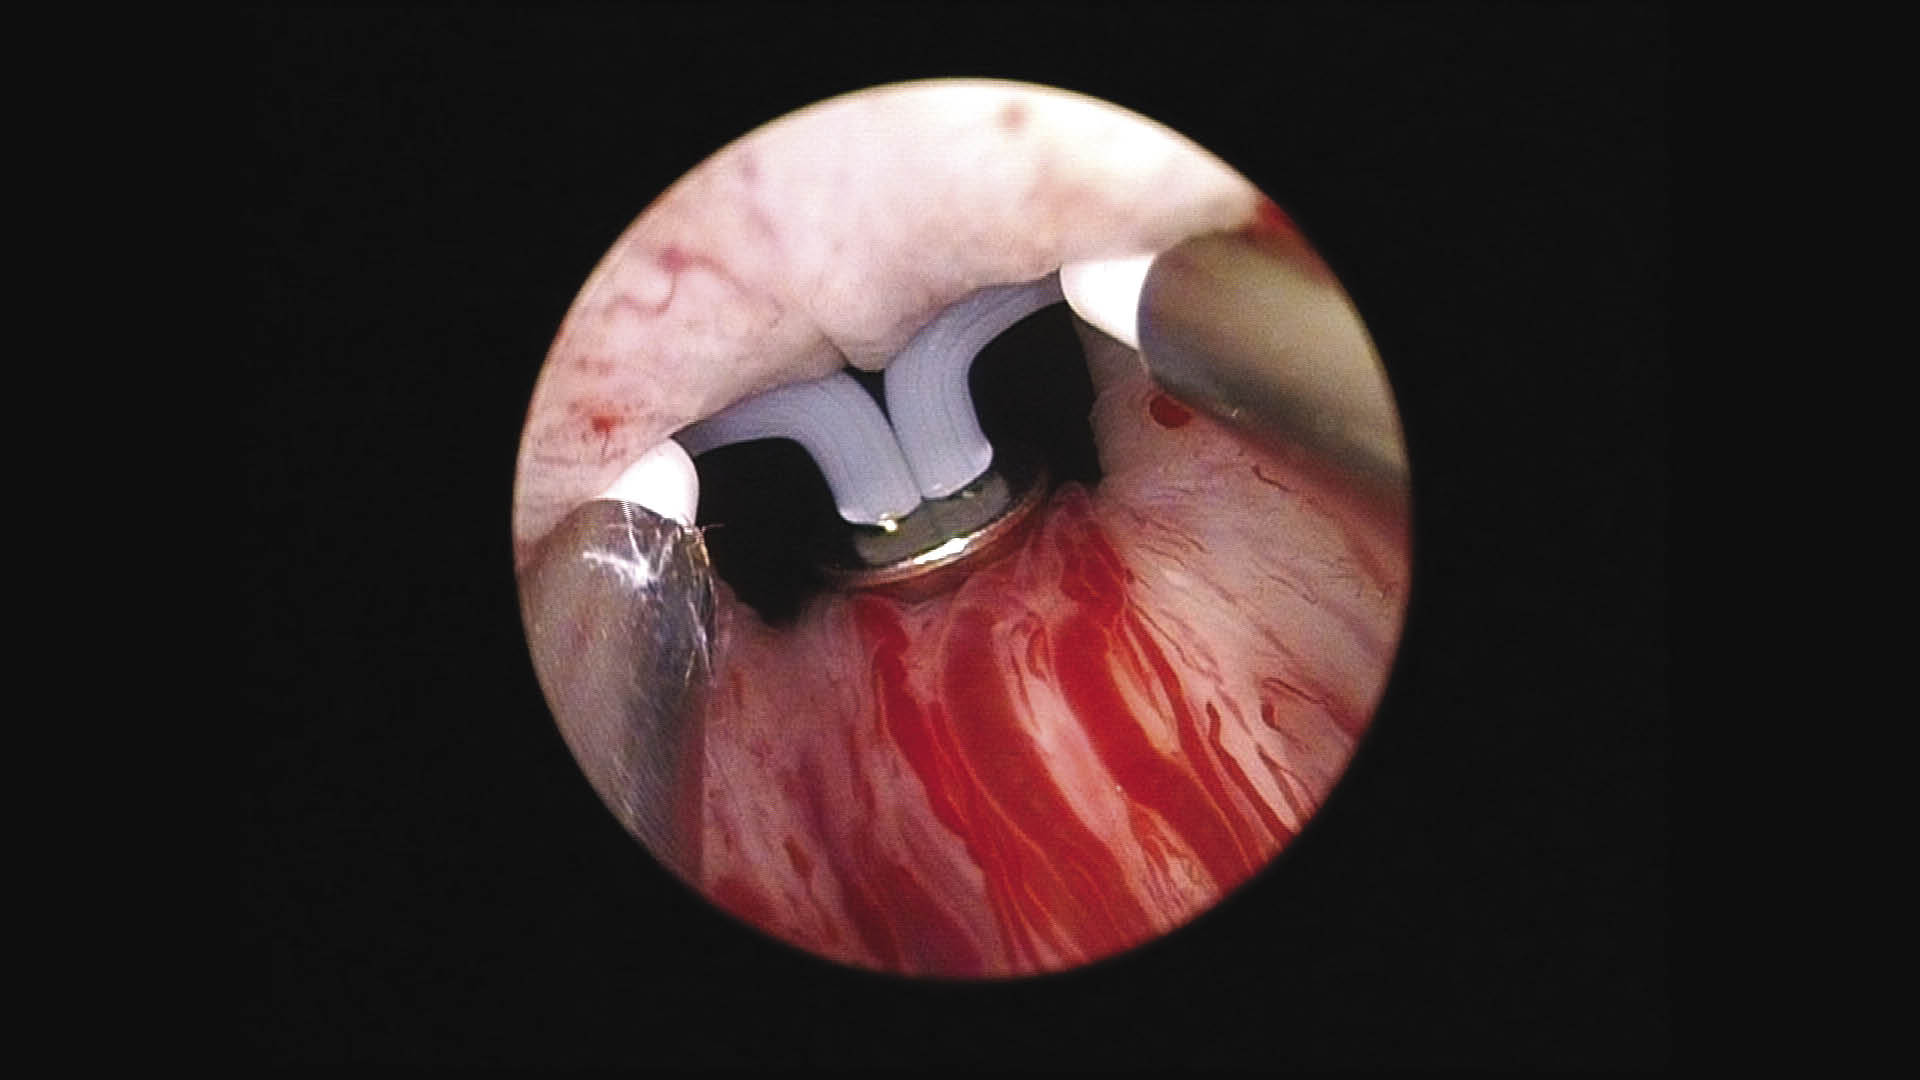

After achieving a wide open prostatic urethra, Figure 3, circular fibers of the capsule are sometimes seen indicating good depth of vaporization. Once a surgeon thinks enough tissue has been resected, decompression of the bladder by draining the irrigation fluid should be done with immediate reinsertion of the working element. At this time, turn on the irrigation fluid again and see if there are any bleeding vessels or tissue that still needs to be resected. This process is repeated multiple times until there are no other bleeding vessels and there is a wide open prostatic urethra with a decompressed bladder. It is common to repeat this step 3-5 times or more to ensure excellent hemostasis and patient outcomes.

Figure 3. End of the case. Image of the treated prostate showing the prostatic opening.

HOW-DO-IT-Fig3.jpg